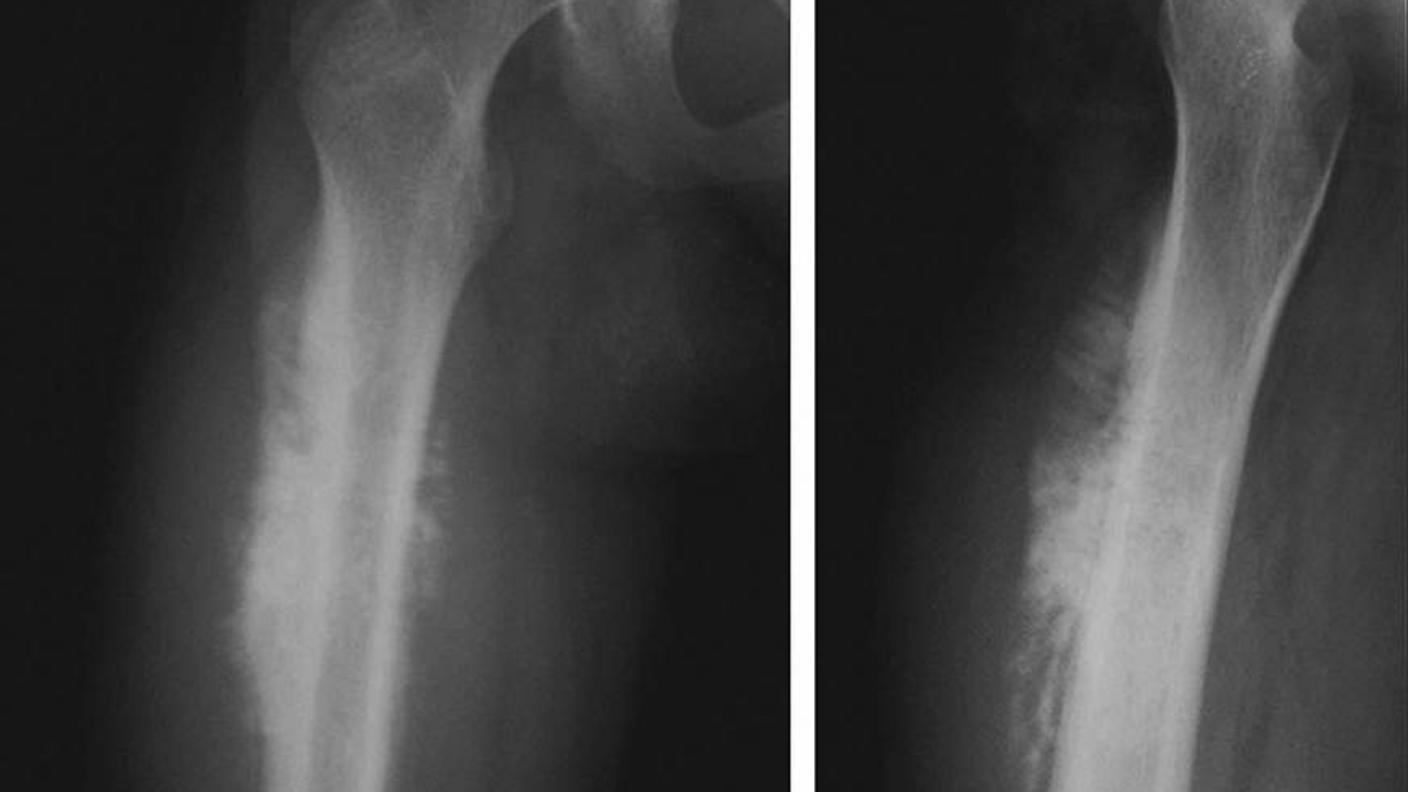

Genetic Studies of Osteosarcoma

Investigators in the Clinical Genetics Branch (CGB) are conducting genetic studies of osteosarcoma to better understand the role that genetic variation plays in risk and patient outcomes, and to identify new genes or genomic regions that may be important in osteosarcoma pathogenesis. The global collaborative effort includes researchers from the Children’s Oncology Group (COG); the University of Minnesota, US; Childhood Cancer Survivor Study, US; Universidad de Navarra, Pamplona, Spain; Institut Curie, France; Istituto Ortopedico Rizzoli, Italy; Royal National Orthopaedic Hospital NHS Trust and University College London Cancer Institute, UK; University of Toronto, Litwin Centre for Cancer Genetics, Canada; Instituto de Oncologia Pediátrica GRAACC/UNIFESP, Brazil; Ankara Oncology and Education Research Hospital, Turkey; The Kinghorn Cancer Centre, Garvan Institute of Medical Research, Australia; Unidad Nacional de Oncologia Pediatrica, Guatemala.